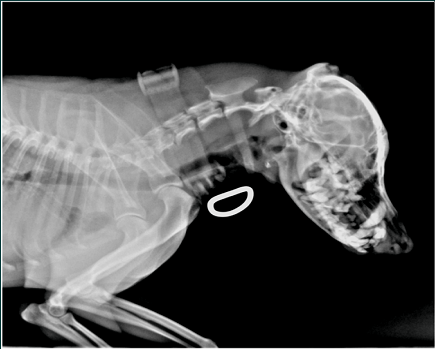

This advanced technology, invented at NASA, employs a carefully designed sequence of magnetic pulses programmed to provide a Pulsed ElectroMagnetic Field (PEMF) around a volume of tissue that is experiencing pain or to assist in the healing process. This biomedical device is designed to safely promote healing in muscle, tendon, ligament, skin, and bone tissues. These tissues make up more than 75% of the weight of the body of animals and humans, and it is often in one or more of these tissues that debilitating injury and pain need to be corrected. Our technology is unique in many respects because it is based upon the physics of electricity and magnetism as well as the physiology of cells and tissues. The MagnaVet device is a Pulsed Electro-Magnetic Field (PEMF) device intended to be used by a pet owner in a home environment after prescription from a qualified veterinarian. The device is intended to safely and effectively promote healing in hard and soft tissue injury and chronic disease states, including, but not limited to, long bone fracture, tendon, ligament, and cartilage injury, and osteoarthritis. PEMF has been demonstrated to reduce localized swelling, induce cell proliferation and extracellular matrix deposition, and promote healing.

The Magnavet is NOT FOR HUMAN USE. The MagnaVet device is intended to safely and effectively promote healing in hard and soft tissue injury and chronic disease states, including, but not limited to, long bone fracture, tendon, ligament, and cartilage injury, and osteoarthritis in pets. It is only available by prescription from a qualified veterinarian, and is expressly not intended to treat food or food-producing animals.